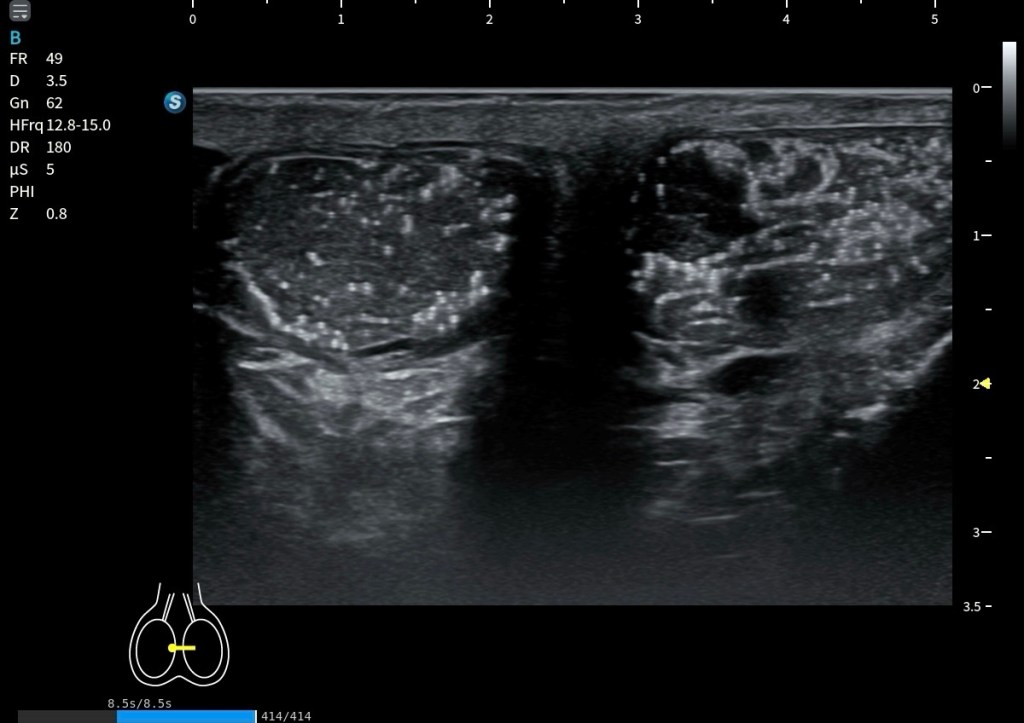

El Platisma se presta especialmente bien a la evaluación mediante técnicas de campo extendido. Utilizando el modo panoramic view, es posible realizar un recorrido continuo del músculo y obtener una visión global de su extensión, algo muy útil dada su morfología plana y superficial.

La exploración puede realizarse en eje axial (corte corto respecto al cuello), desplazando la sonda de forma progresiva a lo largo del trayecto del músculo. Esto permite visualizar su continuidad lateral y entender mejor su disposición en el plano subcutáneo. También puede intentarse un estudio bilateral, tratando de integrar ambos lados en una única imagen panorámica.

Sin embargo, esta técnica presenta cierta dificultad al atravesar la región central del cuello, especialmente sobre la tráquea, donde la superficie es más irregular y la transmisión del movimiento de la sonda es menos homogénea. Esto puede generar artefactos o discontinuidades en la reconstrucción de la imagen.

A pesar de estas limitaciones, el platisma, por ser un músculo muy extenso, plano y superficial, se adapta bien a este tipo de exploración, y la panoramic view se convierte en una herramienta especialmente útil para comprender su anatomía global y su continuidad. Podemos medirlo tambien.